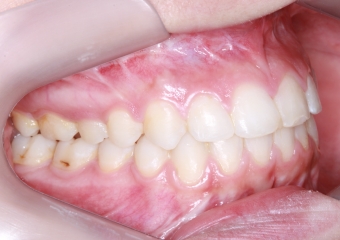

Mordida inicial